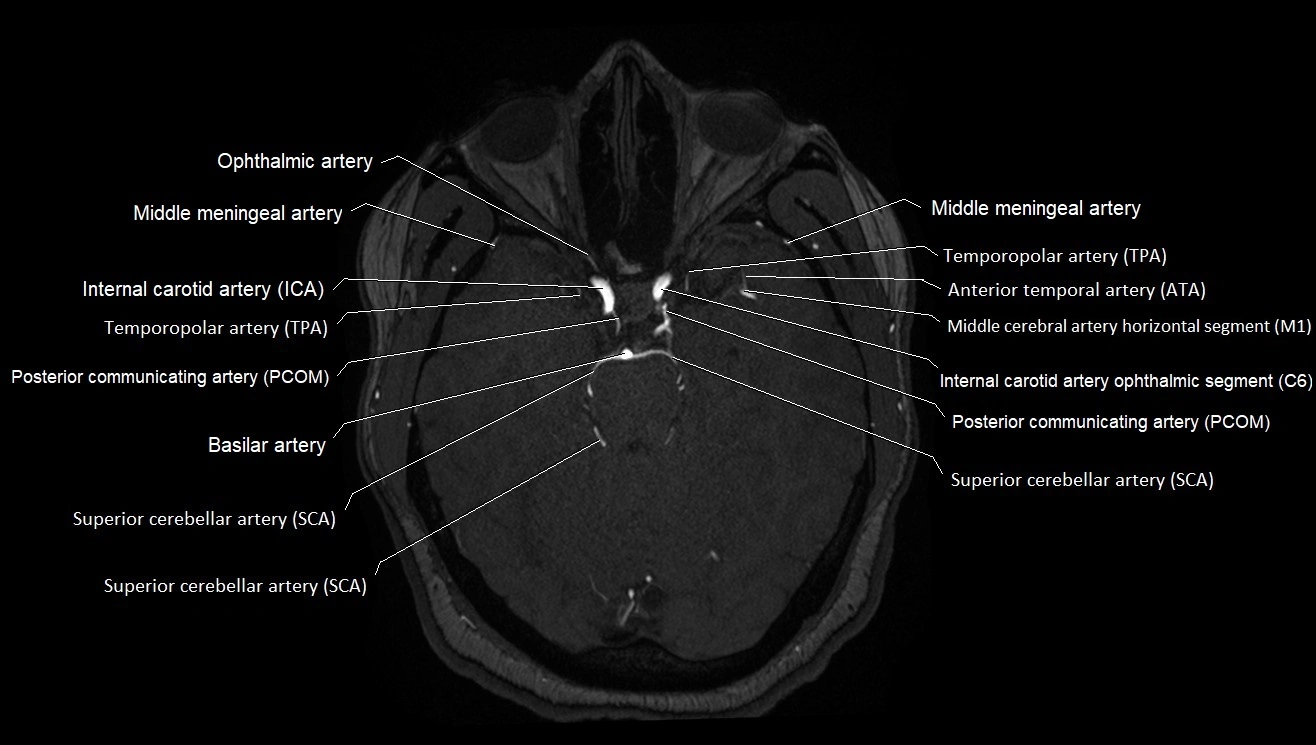

CT images

image